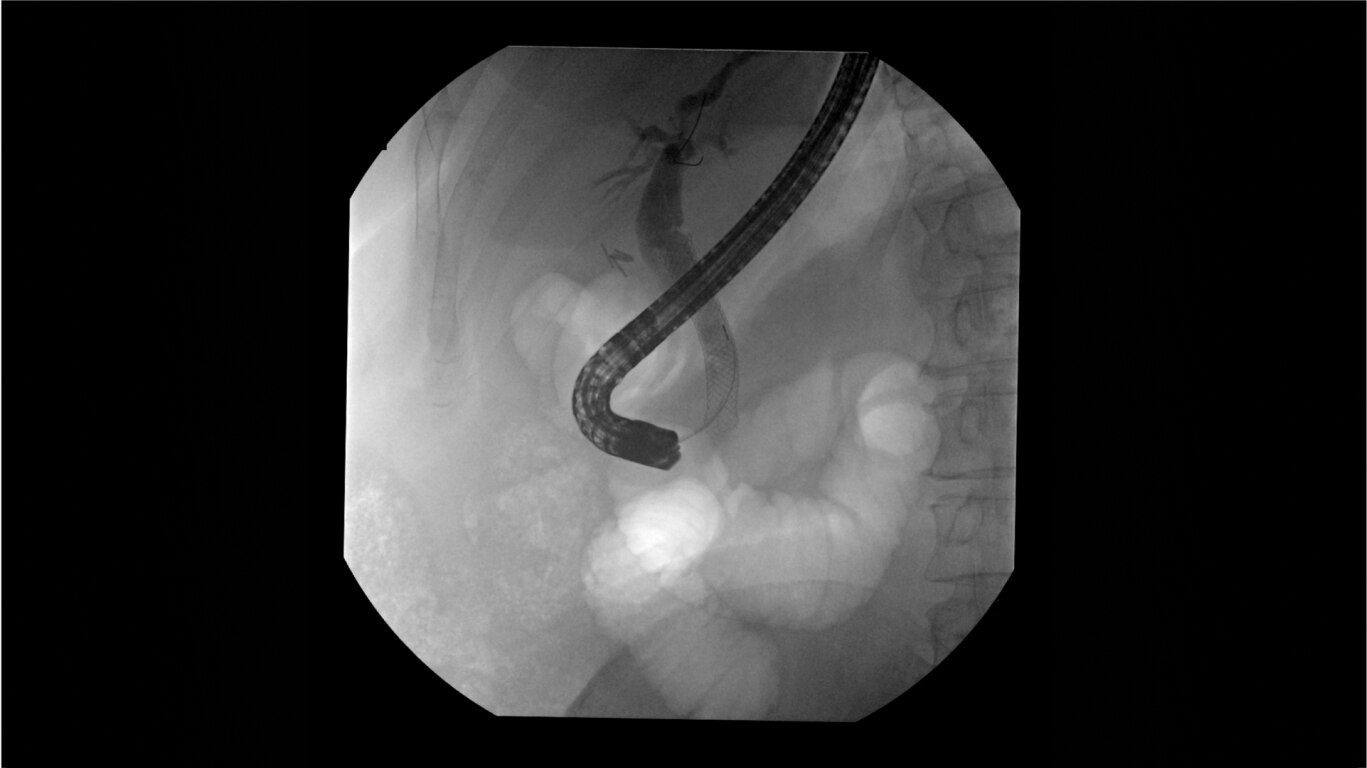

Clearly visualize the GI tract of patients, regardless of size, during a wide range of endoscopic procedures, including ERCP. OEC C-arms offer amazing image quality at low dose and provide enhancements for clear visualization during movement in soft tissue, such as during guidance of low-density drainage tubes or thin biopsy brushes. A large, clear display with comfortable viewing enables effortless workflow.

Complex gastrointestinal procedures require powerful imaging systems. OEC premium C-arms perform in a variety of procedures such as:

• Bariatric gastric embolism

• Pediatric congential duodenal

• Endoscopic retrograde cholangiopancreatography